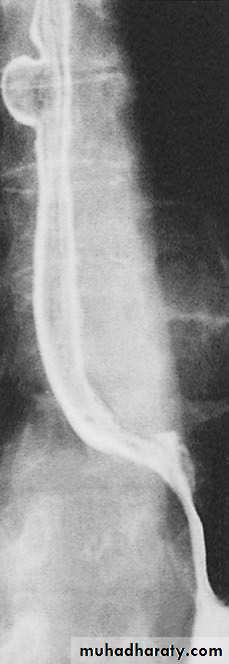

Diagnosis by manometry, and corkscrew esophagus at barium swallow.

Figure9: Corkscrew oesophagus in diffuse oesophageal spasm